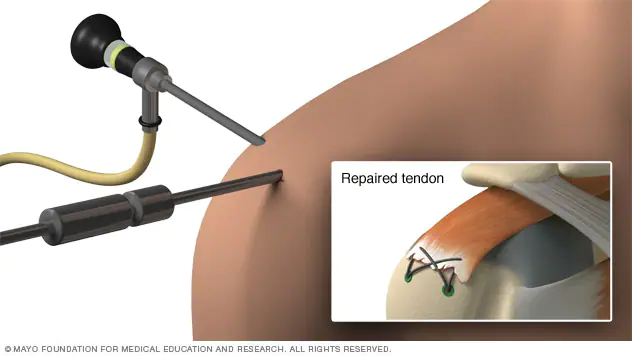

-Artroscopia:

Utilizando un equipo especial de alta tecnología, se visualiza la articulación a traves de una cámara y fibra optica, se colocan pequeños tubos especiales para introducir instrumental y suturas a la articulación y así poder reparar el tendón lesionado. Como ventaja, es mucho menor el daño a los músculos del hombro y la recuperación inicial es más rápida. Cirugía compleja que requiere un cirujano entrenado especialmente en esta técnica.

Puede realizarse una reparación artroscópica, una tenotomía (corte del tendón) y este tendón se puede dejar libre (pacientes mayores), se puede suturar a tejidos blandos o se puede anclar al hueso en una nueva posición (pacientes jóvenes).